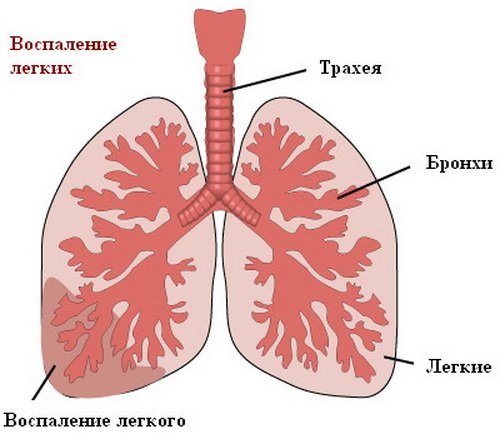

Медицинская тема: легочные осложнения при пневмонии